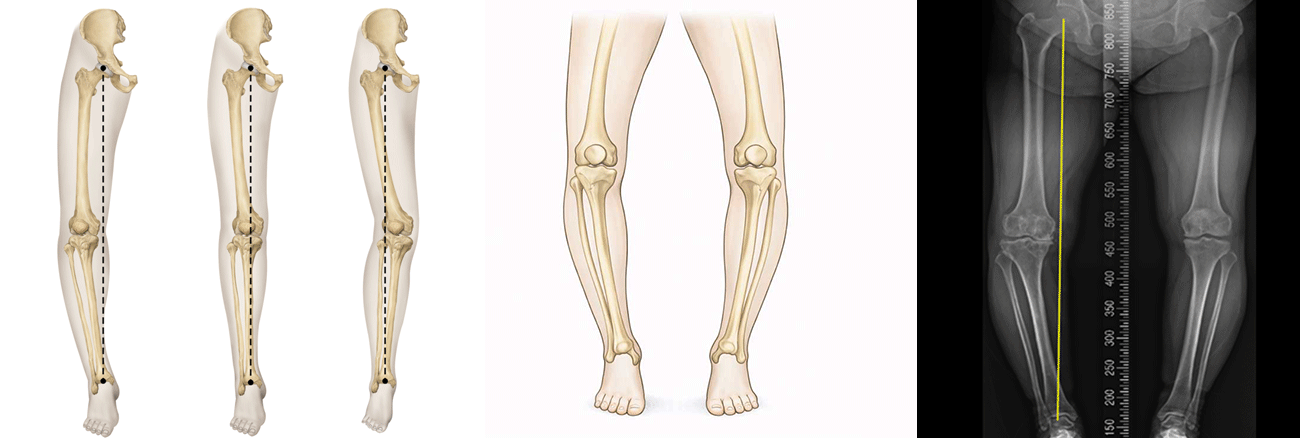

Knee varus malalignment

오다리 변형은 서 있을 때 발은 붙어 있지만 무릎 사이가 벌어지는 다리 정렬 이상을 말합니다. 무릎이 바깥쪽으로 휘어지면서 체중이 무릎 안쪽에 집중되어 전달되는 것이 특징입니다. 초기에는 눈에 띄는 통증이 없을 수 있으나, 시간이 지나면서 무릎 안쪽 통증, 오래 서 있거나 걸을 때 불편감, 보행 시 피로감 등이 나타날 수 있습니다.

오다리 변형은 선천적인 다리 정렬 문제, 성장 과정에서의 잘못된 하중 분포, 반복적인 무릎 사용, 체중 증가 등 다양한 원인으로 발생할 수 있습니다. 특히 무릎 안쪽 관절에 지속적으로 과도한 하중이 가해지면 연골 손상이 빨라지면서 변형이 점점 심해질 수 있습니다. 이러한 정렬 이상은 퇴행성 관절염의 진행을 앞당기는 원인이 되기도 합니다.